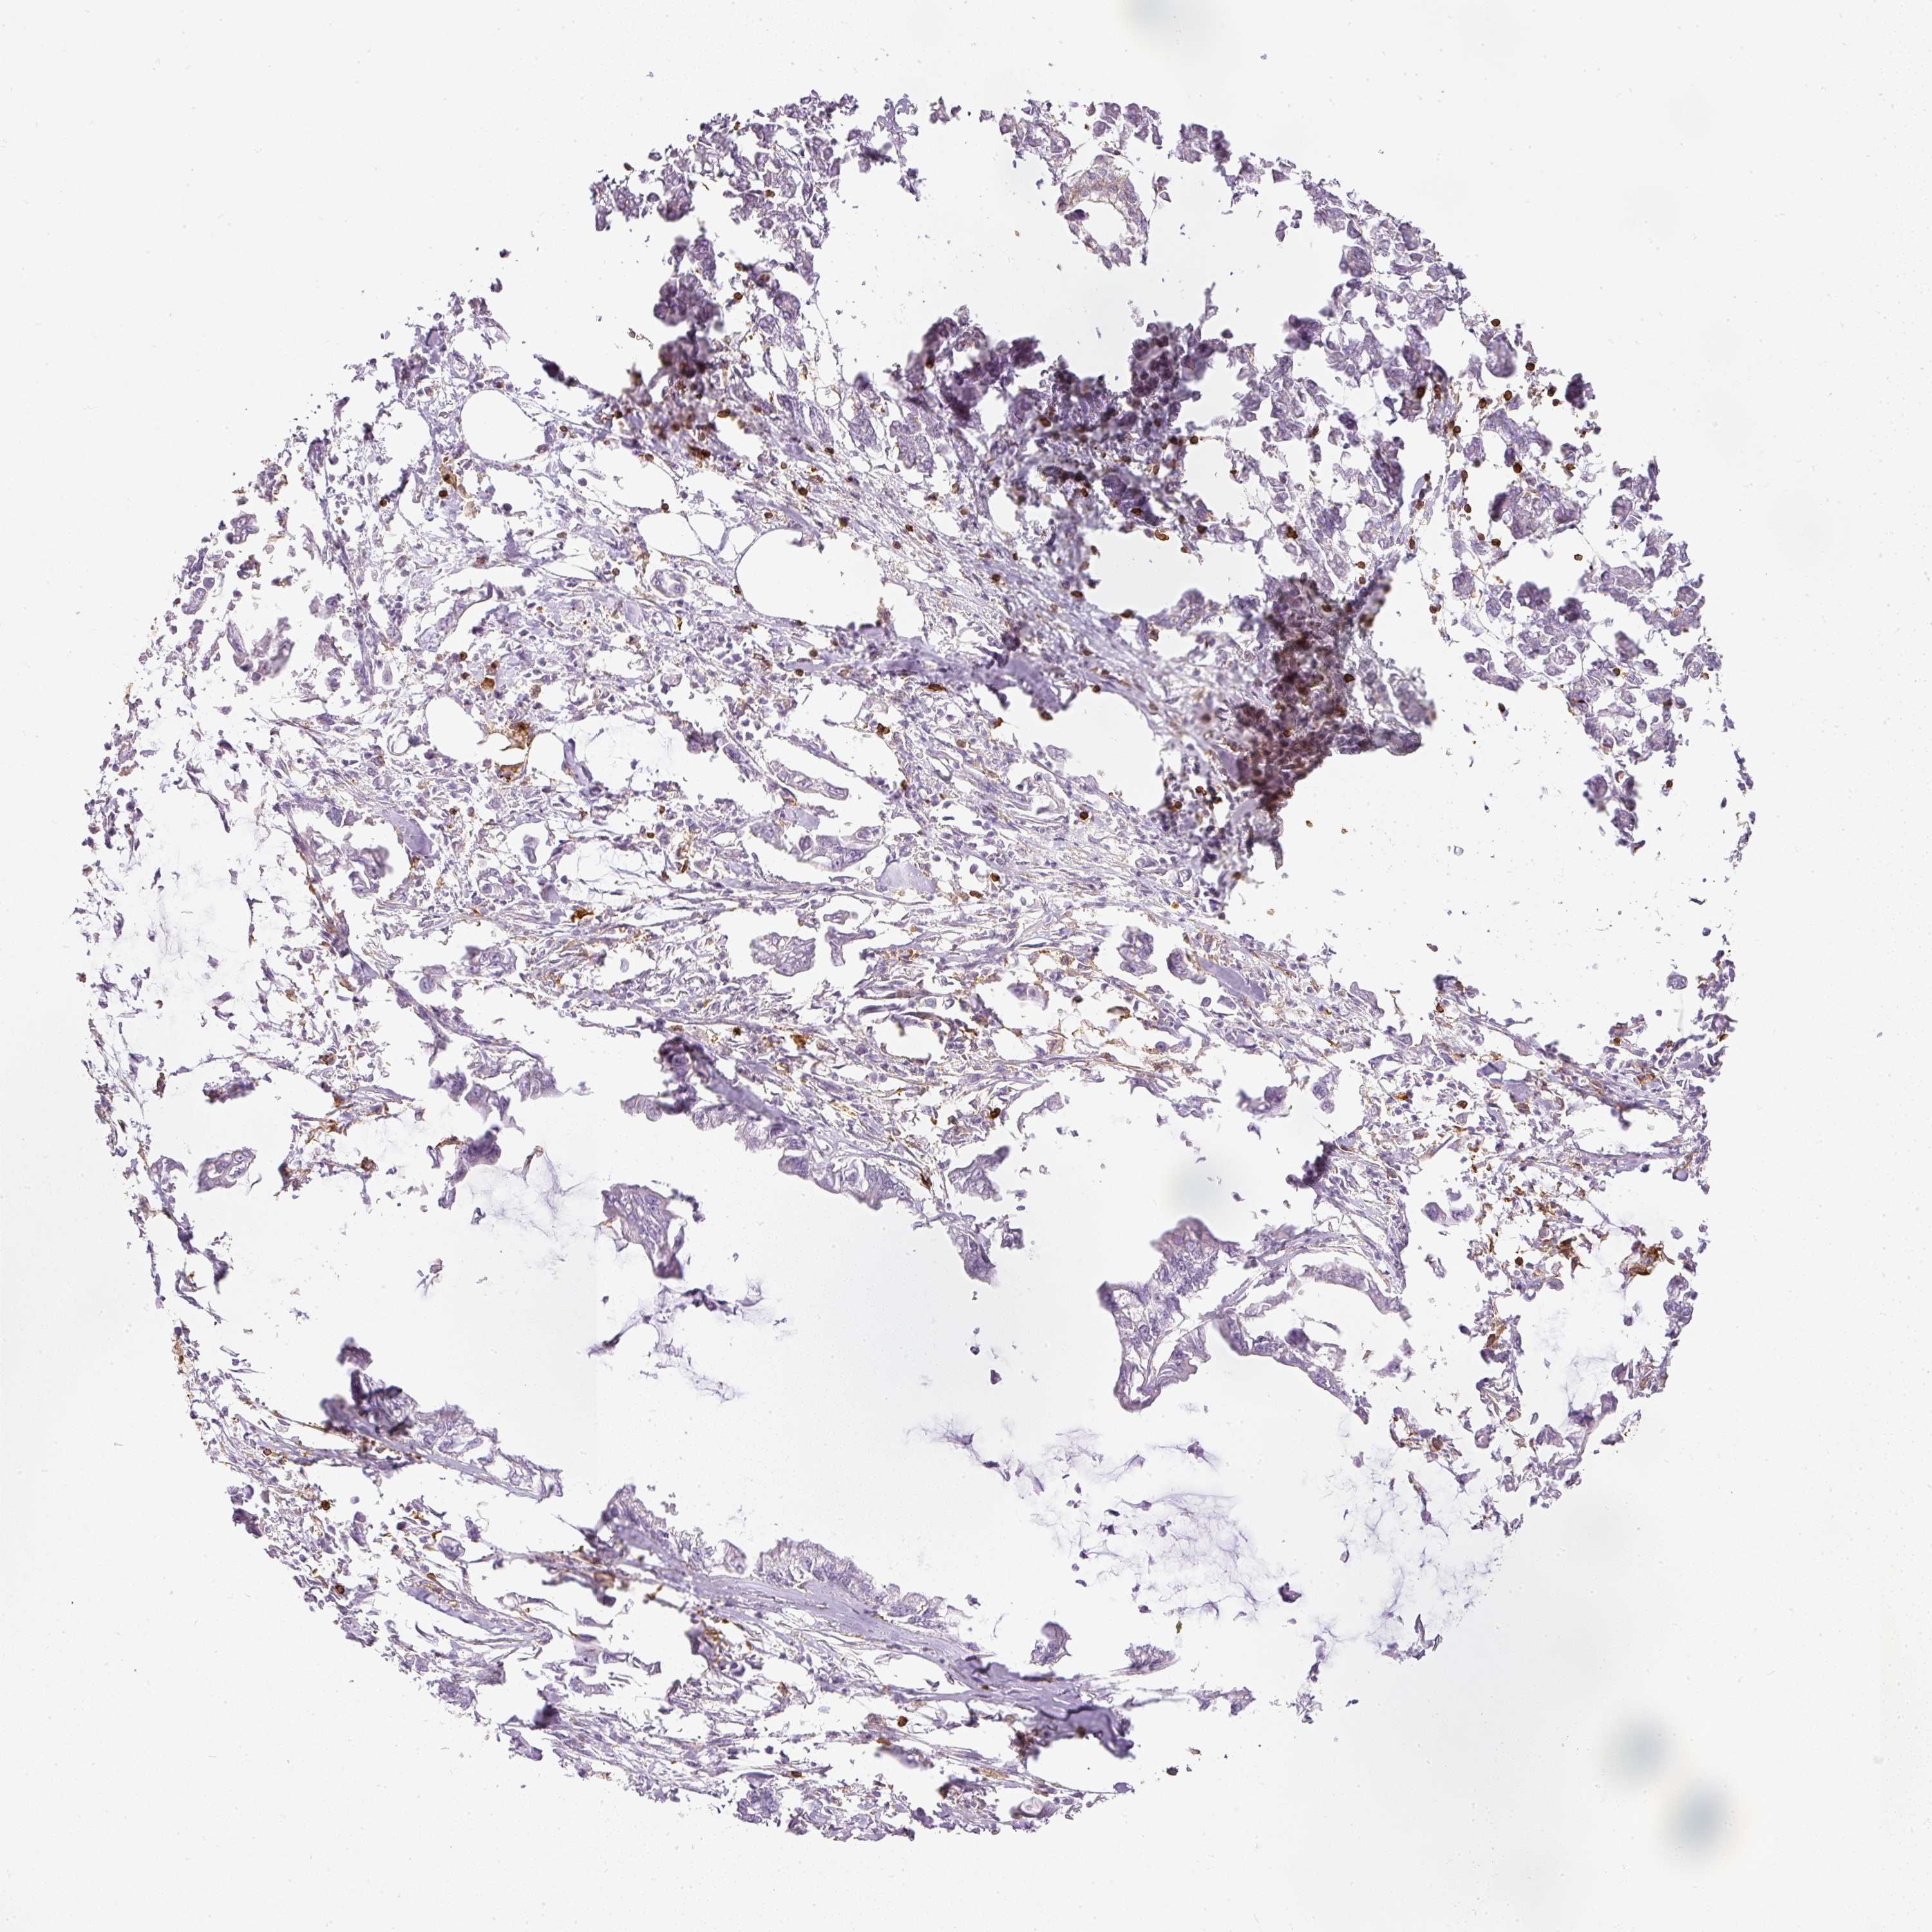

PANCREATIC CANCER - Protein expressioni

A mouse-over function shows sample information and annotation data. Click on an image to view it in a full screen mode. Samples can be filtered based on level of antibody staining by selecting one or several of the following categories: high, medium, low and not detected. The assay and annotation is described here.

Note that samples used for immunohistochemistry by the Human Protein Atlas do not correspond to samples in the TCGA dataset.

Antibody stainingi

Antibody staining in the annotated cell types in the current human tissue is reported as not detected, low, medium, or high, based on conventional immunohistochemistry profiling in selected tissues. This score is based on the combination of the staining intensity and fraction of stained cells.

Each image is clickable and will lead to virtual microscopy that enables deeper exploration of all samples and also displays staining intensity scores, fraction scores and subcellular localization as well as patient and tissue information for each sample.

Antibody HPA018849

Antibody HPA019536

Antibody CAB033987

Adenocarcinoma, NOS